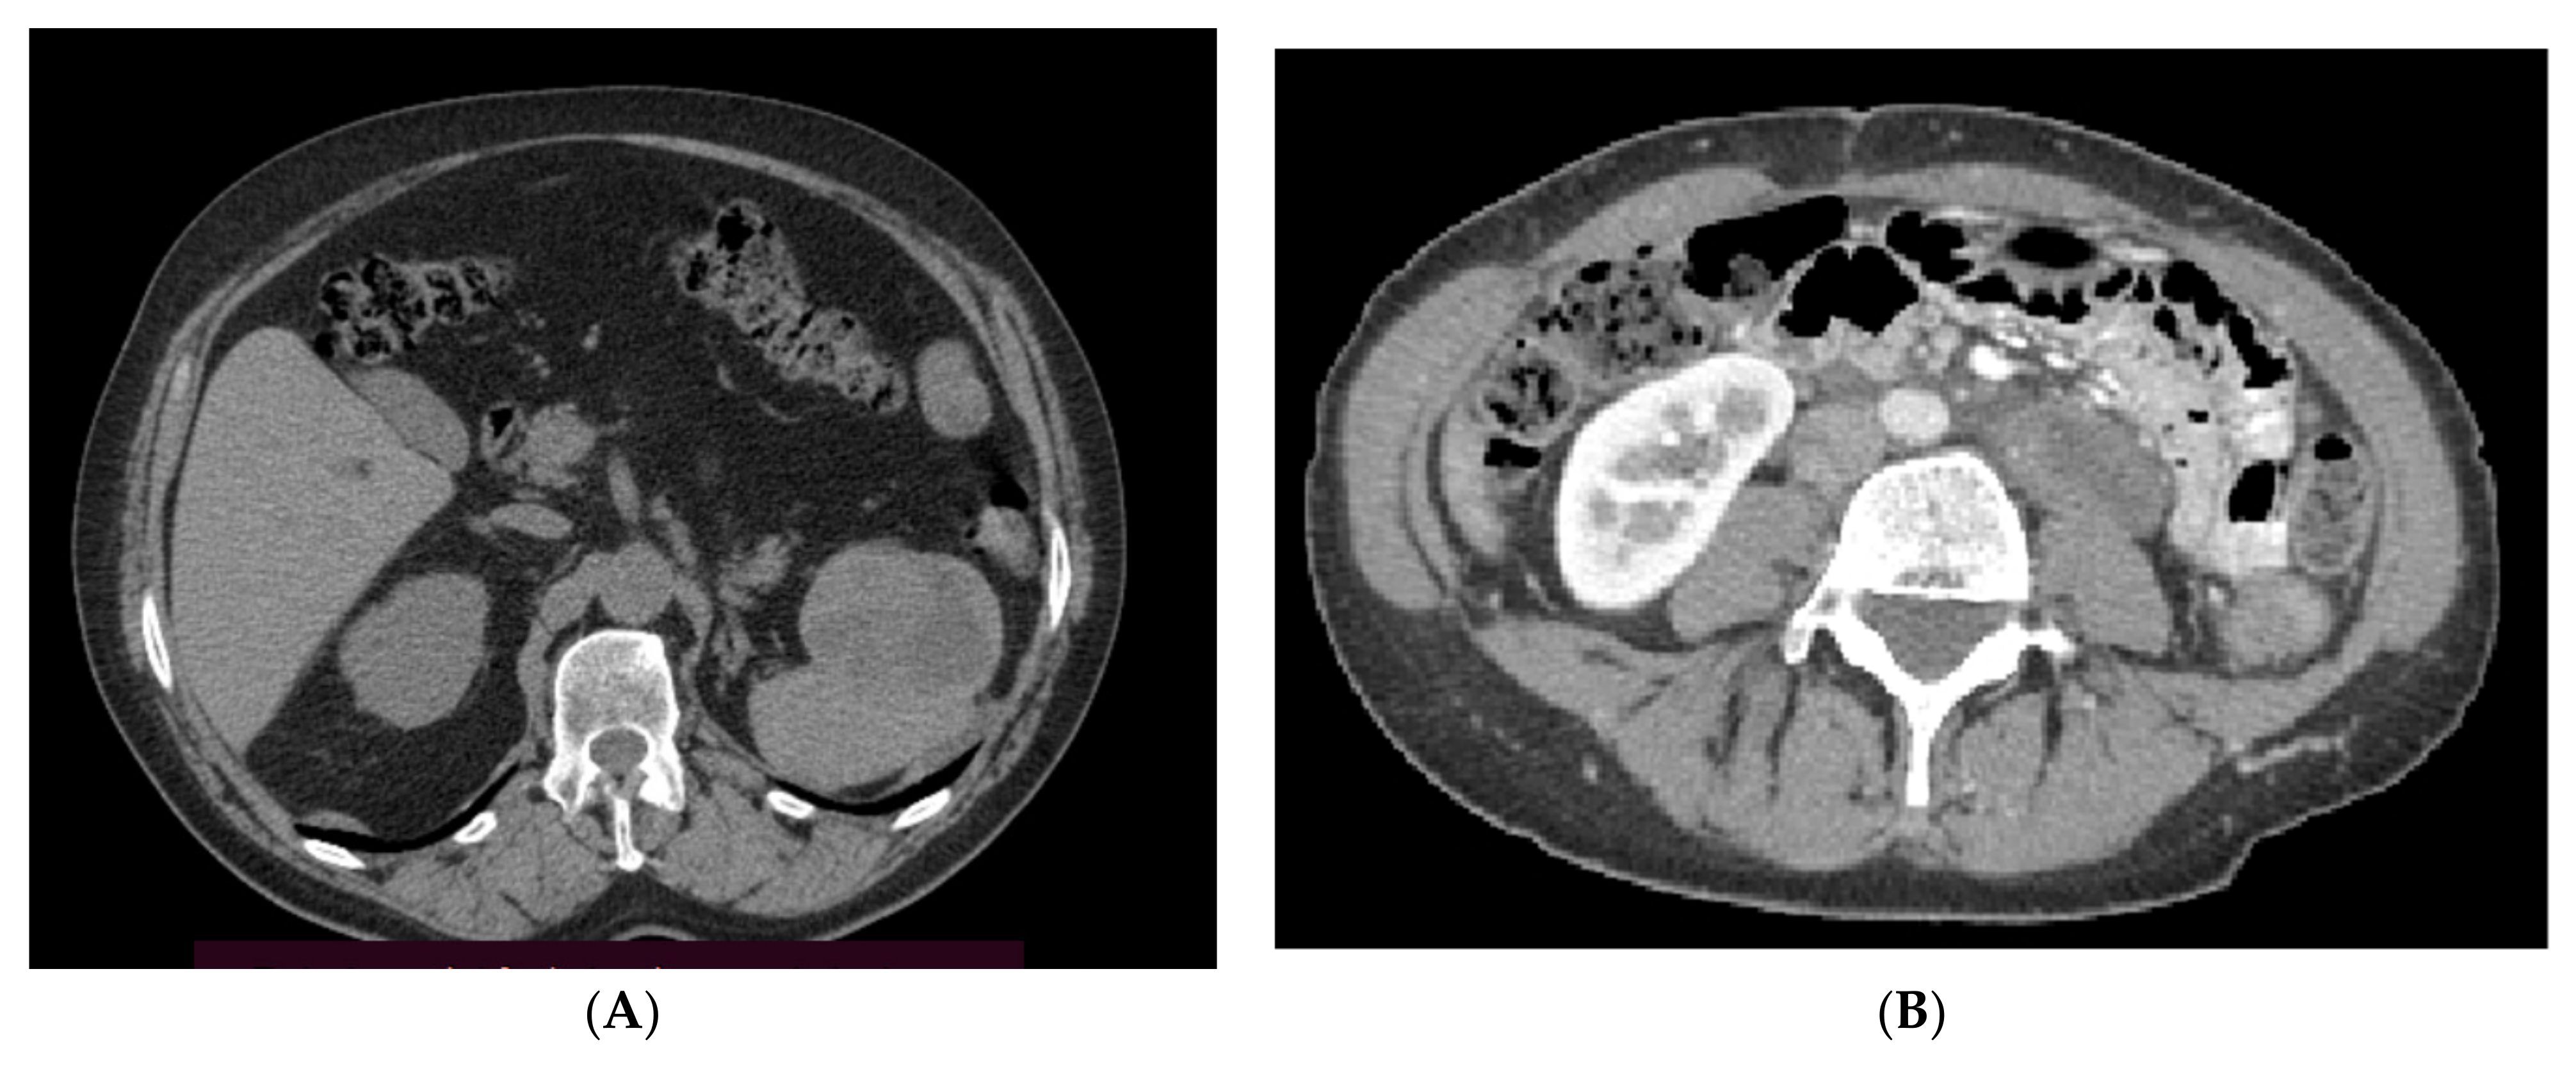

- Tirumani, S.H.; Shinagare, A.B.; Hargreaves, J.; Jagannathan, J.P.; Hornick, J.L.; Wagner, A.J.; Ramaiya, N.H. Imaging features of primary and metastatic malignant perivascular epithelioid cell tumors. AJR Am. J. Roentgenol. 2014, 202, 252–258. [Google Scholar] [CrossRef] [PubMed]